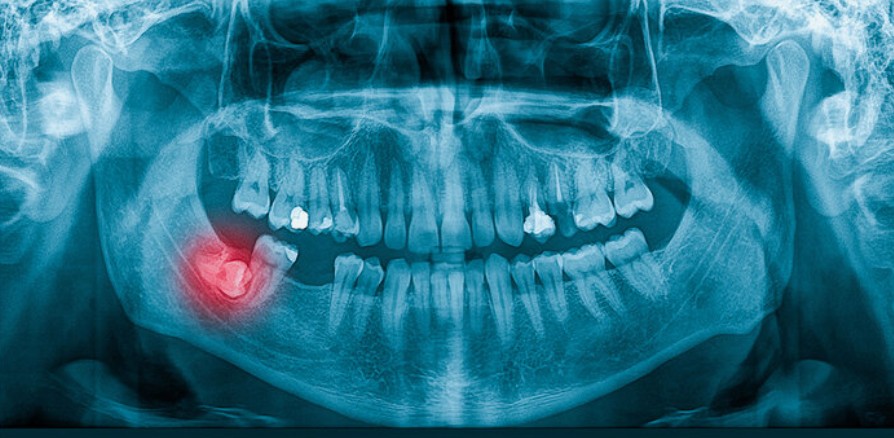

Khi nào nên đi khám?

Ngay khi xuất hiện các dấu hiệu đau vùng hàm sau, sưng lợi, hoặc nghi ngờ răng khôn mọc lệch, bạn nên đến nha sĩ để chụp X-quang. Phim X-quang toàn hàm (Panorama) giúp xác định chính xác hướng mọc, độ nghiêng và mức độ ảnh hưởng đến các răng khác.

3. Tầm quan trọng của phim X-quang toàn hàm (Panorama)

Chụp phim toàn hàm là phương pháp chính xác nhất để xác định:

- Có bao nhiêu răng khôn.

- Hướng mọc của từng răng (thẳng, lệch, ngang, ngầm).

- Mức độ ảnh hưởng đến răng số 7 hoặc dây thần kinh hàm dưới.

Các nha sĩ thường khuyến nghị chụp phim kiểm tra khi bạn ở độ tuổi 17-20, ngay cả khi chưa thấy dấu hiệu mọc răng khôn, nhằm phát hiện sớm nguy cơ và lên kế hoạch xử lý phù hợp.